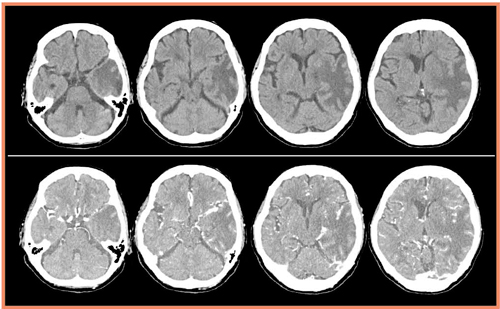

通常の単純撮影と造影CTの画像(図5)では,MRI以上の情報は認められないが,ボリュームキャンでCTA(図6)を行ったところ,左横静脈洞からの頸静脈にかけて,順行性の血流がないことが確認できた(↓)。CTを行うことにより,静脈性の梗塞という診断を確定することが可能になった。その後,保存的に加療され,1年経過した現在も患者の予後は良好である。

図5 症例をAquilion ONEで撮影

a:単純CT画像(上段)

b:造影CT画像(下段)